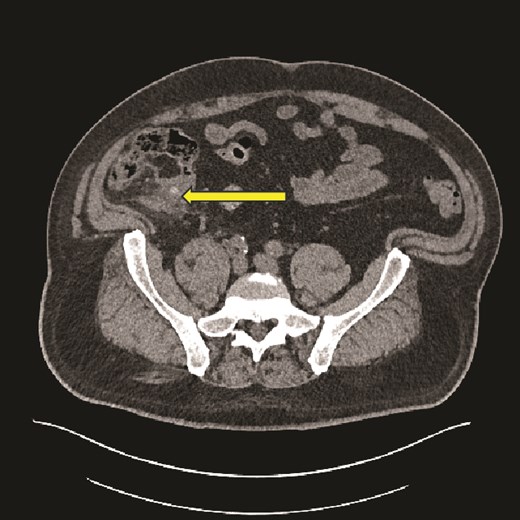

Computed tomography (CT) scan abdomen and pelvis was reported as follows: ‘Inflammatory phlegmon, fat stranding, free fluid, and reactive lymphadenopathy in the right iliac fossa. At the centre of the inflammatory phlegmon there is a dilated appendix with thickened walls. Small appendicolith at the base. Incidental note of a 3.2 cm caecal lipoma, which resides just below the ileocecal valve.’ (Figs 1–3).

Axial CT image showing caecal inflammation and peri caecal stranding (arrow).